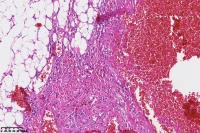

海绵状血管瘤?

楼主 发表于 2023-02-19 09:49

性别

男

年龄

31岁

临床诊断

一般病史

颈部包块

标本名称

大体所见

图1

同意楼主意见,海绵状血管瘤。